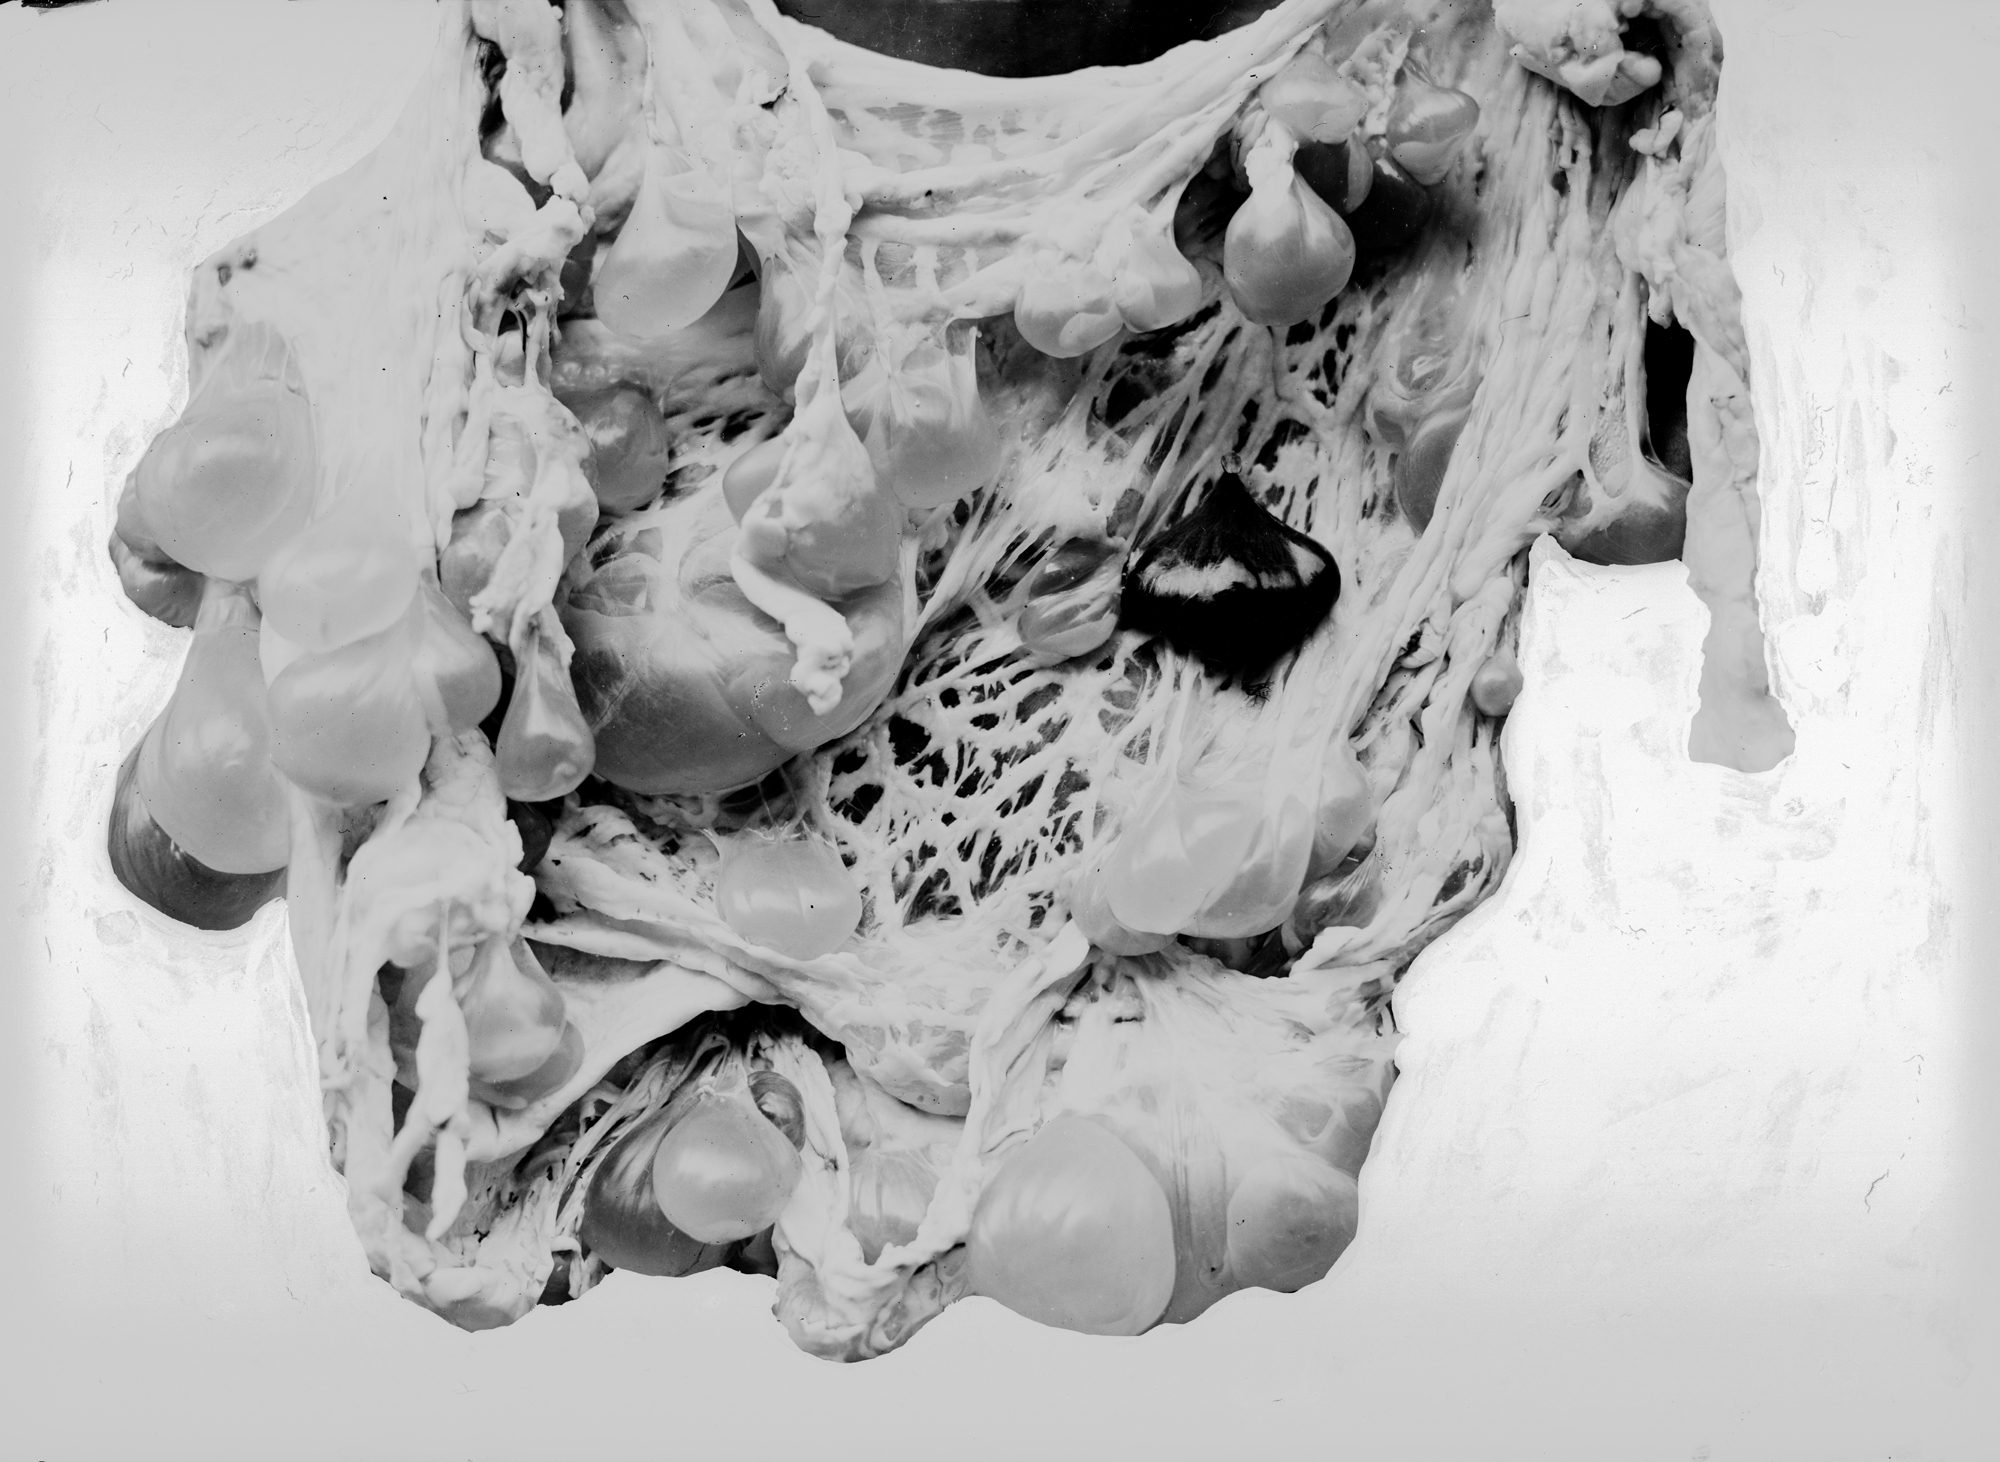

Pathological specimens of Hydatids cysts

January 1921–December 1935